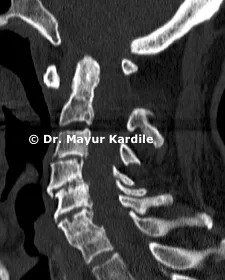

Diagnosis

• X-rays including dynamic flexion-extension views • CT scan of the upper cervical spine • MRI to assess spinal cord compression • Careful neurological examination